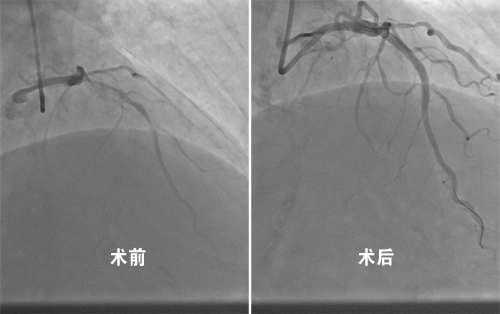

12月26日,临床医学院/附属医院心血管内科黄问银团队首次运用刚引进的血管内超声诊断仪(intravenous ultrasound,IVUS)和冠状动脉内膜旋磨技术(eoronary trartsluminal rotational atherectomy,Rotablator),成功地为一位冠脉严重钙化伴狭窄的78岁男性患者,完成了一台高难度的冠脉支架植入手术。手术历时1个多小时,有效地解决了患者多年心绞痛症状,避免了因血管钙化导致的术中风险和操作难度。

血管内超声和冠状动脉内膜旋磨技术,是当前国内外冠心病介入治疗领域的两项先进技术,已成为技术精湛专家们解决复杂高风险冠脉病变的有利武器。目前,附院心内科介入团队在复杂冠脉病变,尤其是冠脉慢性完全闭塞病变(CTO)介入治疗方面,逐步地形成了技术优势和特点,近几年来已完成CTO介入手术60余台,多次受邀参加国内、省内会议手术视频现场直播,这两项技术的成功运用标志着该院冠脉介入技术水平已步入了全省领先行列。